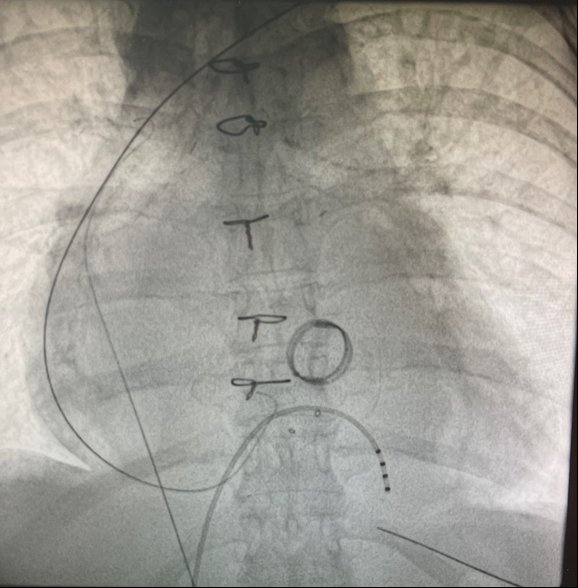

🫀 RISCONTRO OCCASIONALE DI TROMBO IN AURICOLA ATRIALE DESTRA IN UN GIOVANE PAZIENTE CON SCOMPENSO CARDIACO CONGESTIZIO E IN RITMO SINUSALE🫀

📌Caso clinico: italiancot.it/2023/06/03/ris…